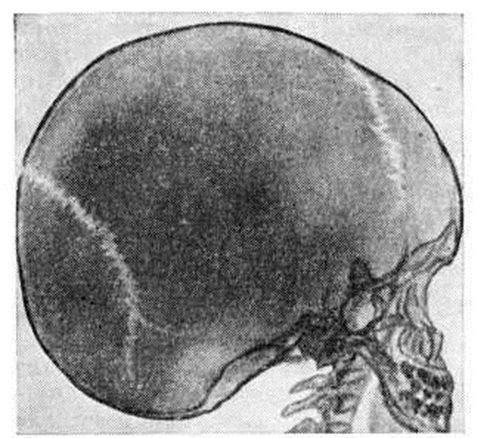

ГидроцефалияГидроцефалия (hydrocephalus; греческий hydor вода + kephale голова; синонимы водянка головного мозга) — состояние, характеризующееся избыточным накоплением цереброспинальной жидкости в желудочках мозга и подоболочечных пространствах. Гидроцефалия является следствием различных заболеваний или травм головного мозга и его оболочек. КлассификацияНаибольшее распространение в СССР получила классификация, предложенная А. А. Арендтом в 1948 год. В ней Гидроцефалия рассматривается в зависимости от времени возникновения, течения, этиологического факторов, локализации и характера нарушения функции ликворного аппарата. По времени возникновения различают врождённую и приобретённую Гидроцефалия, по течению — острую и хроническую. По локализации выделяют наружную и внутреннюю Гидроцефалия При наружной Гидроцефалия имеется избыточное скопление цереброспинальной жидкости преимущественно в субарахноидальных пространствах, при внутренней — в желудочках головного мозга. Нередко наблюдается комбинация внутренней и наружной Гидроцефалия — так называемый общая Гидроцефалия По характеру нарушения функции ликворного аппарата принято различать открытую (сообщающуюся) и закрытую (окклюзионную) Гидроцефалия Открытую Гидроцефалия в свою очередь подразделяют на гиперсекреторную, при которой секреция цереброспинальной жидкости значительно повышена, и арезорбтивную, характеризующуюся нарушением её всасывания. При окклюзионной Гидроцефалия имеется нарушение на различных уровнях оттока цереброспинальной жидкости из желудочков в субарахноидальные пространства в результате спаечного процесса, кист, опухолей и так далее. Встречаются смешанные формы Гидроцефалия, когда окклюзия ликворных путей сочетается с нарушением резорбции или секреции цереброспинальной жидкости. Этиология и патогенезРазличные поражения головного мозга и его оболочек могут привести к Гидроцефалия Чаще всего она наблюдается после инфекционных заболеваний (гнойный эпидемический цереброспинальный менингит, вторичные менингиты и менингоэнцефалиты) и черепно-мозговых травм. Кроме того, Гидроцефалия может возникнуть при затруднении оттока крови из полости черепа (патология венозной системы, тромбоз синусов, сдавление рубцами и спайками отводящих вен), при опухолях, а также при гипертензии, заболеваниях почек и паразитарных поражениях головного мозга. Иногда Гидроцефалия возникает в результате аномалии развития головного и спинного мозга (недоразвитие мозга, мозговые и спинномозговые грыжи и так далее). Вышеперечисленные причины могут привести к нарушению секреции, всасывания или циркуляции цереброспинальной жидкости с последующим развитием Гидроцефалия Патологическая анатомияМорфологически изменения в мозге и оболочках при Гидроцефалия зависят как от основного заболевания, приведшего к Гидроцефалия, так и от длительности повышенного внутричерепного давления. Как правило, наблюдается расширение полостей желудочков, особенно боковых, за счёт увеличения в них количества цереброспинальной жидкости (рисунок 1). Боковые желудочки расширены симметрично как при открытой, так и закрытой Гидроцефалия с окклюзией межжелудочковых отверстий водопровода мозга и апертур IV желудочка (рисунок 2—4). |

Асимметричное расширение желудочков чаще всего наблюдается при закупорке одного межжелудочкового отверстия или на стороне травмы. Прогрессирующее увеличение желудочков приводит к атрофии мозговой ткани, уплощению извилин и сглаживанию борозд мозга. Рано поражаются пирамидные пути. Изменению подвергается прежде всего белое вещество, мозолистое тело и свод. Изменение серого вещества наблюдается при Гидроцефалия в результате травмы и в тяжёлых случаях Гидроцефалия. При врождённой Гидроцефалия может нарушаться строение коры. Атрофия нервной ткани при Гидроцефалия, по мнению У. Пенфилда и Элвиджа (A. Elwidge, 1932), Б. Н. Клосовского (1949), В. П. Пурина (1968), происходит в результате сдавления капилляров мозга вследствие внутричерепной гипертензии. Выраженная астроцитарная реакция в белом веществе при Гидроцефалия является плохим прогностическим признаком. Кроме изменений со стороны ткани мозга, при Гидроцефалия отмечают выраженные изменения и со стороны сосудистых сплетений, эпендимы желудочков и его оболочек. Наблюдается атрофия сосудистых сплетений с фиброзным перерождением их соединительнотканной основы и гибелью эпителия. При Гидроцефалия после инфекционных заболеваний выявляют признаки гранулематозного эпендиматита (смотри Хориоэпендиматит). Мозговые оболочки резко утолщены, мутны, отёчны. Отмечают их фиброз, сращение главным образом в области базальных цистерн основания мозга, большого затылочного отверстия и апертур IV желудочка. В оболочках выявляют воспалительные инфильтраты. При травматической Гидроцефалия в мозге находят следы бывших кровоизлияний, рубцы в местах некрозов мозговой ткани, спайки в области путей оттока цереброспинальной жидкости и так далее. В сосудах головного мозга при Гидроцефалия обнаруживают признаки артериосклероза с гиалинозом сосудов.